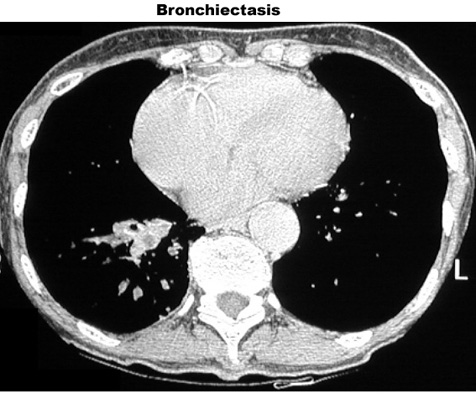

Bronchiectasis

Dilated bronchi with peribronchial fibrosis, visualized in various cuts of CT as cystic spaces, tubular shadows and branching densities.